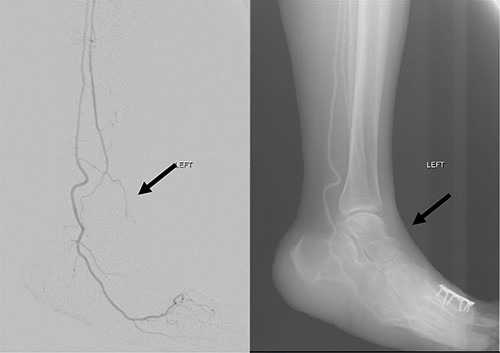

Mdm. S.N.C is a 59-year-old lady with a background of hypertension and diabetes mellitus who had corrective surgery for her left hallux valgus deformity in July 2020 (Fig. 1). This was complicated by wound dehiscence and exposure of the underlying tendon (Extensor hallucis longus) and implant (Fig. 2). An arterial duplex scan was done, which showed 70–80% occlusive disease over the proximal anterior tibial artery (ATA; Fig. 3) that likely contributed to her poor wound healing.

She subsequently underwent left lower limb angioplasty and stenting of the ATA with good results (Figs 4–7) and was started on antiplatelet therapy. Following successful angioplasty, she underwent early wound coverage procedure. A medially based rotation advancement flap was raised for coverage of wound defect. Patient completed 2 weeks course of broad-spectrum antibiotics post-operatively. Patient’s flap was stable and she was allowed partial weight bear over her left lower limb with Darco shoes at post-operative Day 12.

Left lower limb diagnostic angiogram showing occlusion of the ATA with poor flow (arrow).

Angiogram of left distal leg and foot showing poor flow of the distal ATA and dorsalis pedis artery (arrow).